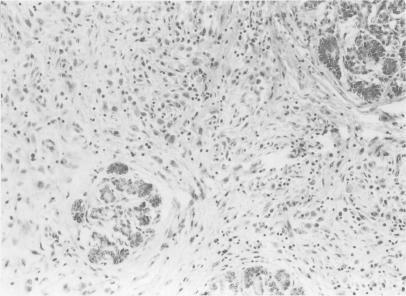

Multisystem Langerhans' cell histiocytosis with pancreatic involvement.

Langerhans cell histiocytosis infiltration into pancreas and kidney.

Langerhans' Cell Histiocytosis Masquerading as Caroli's Disease.